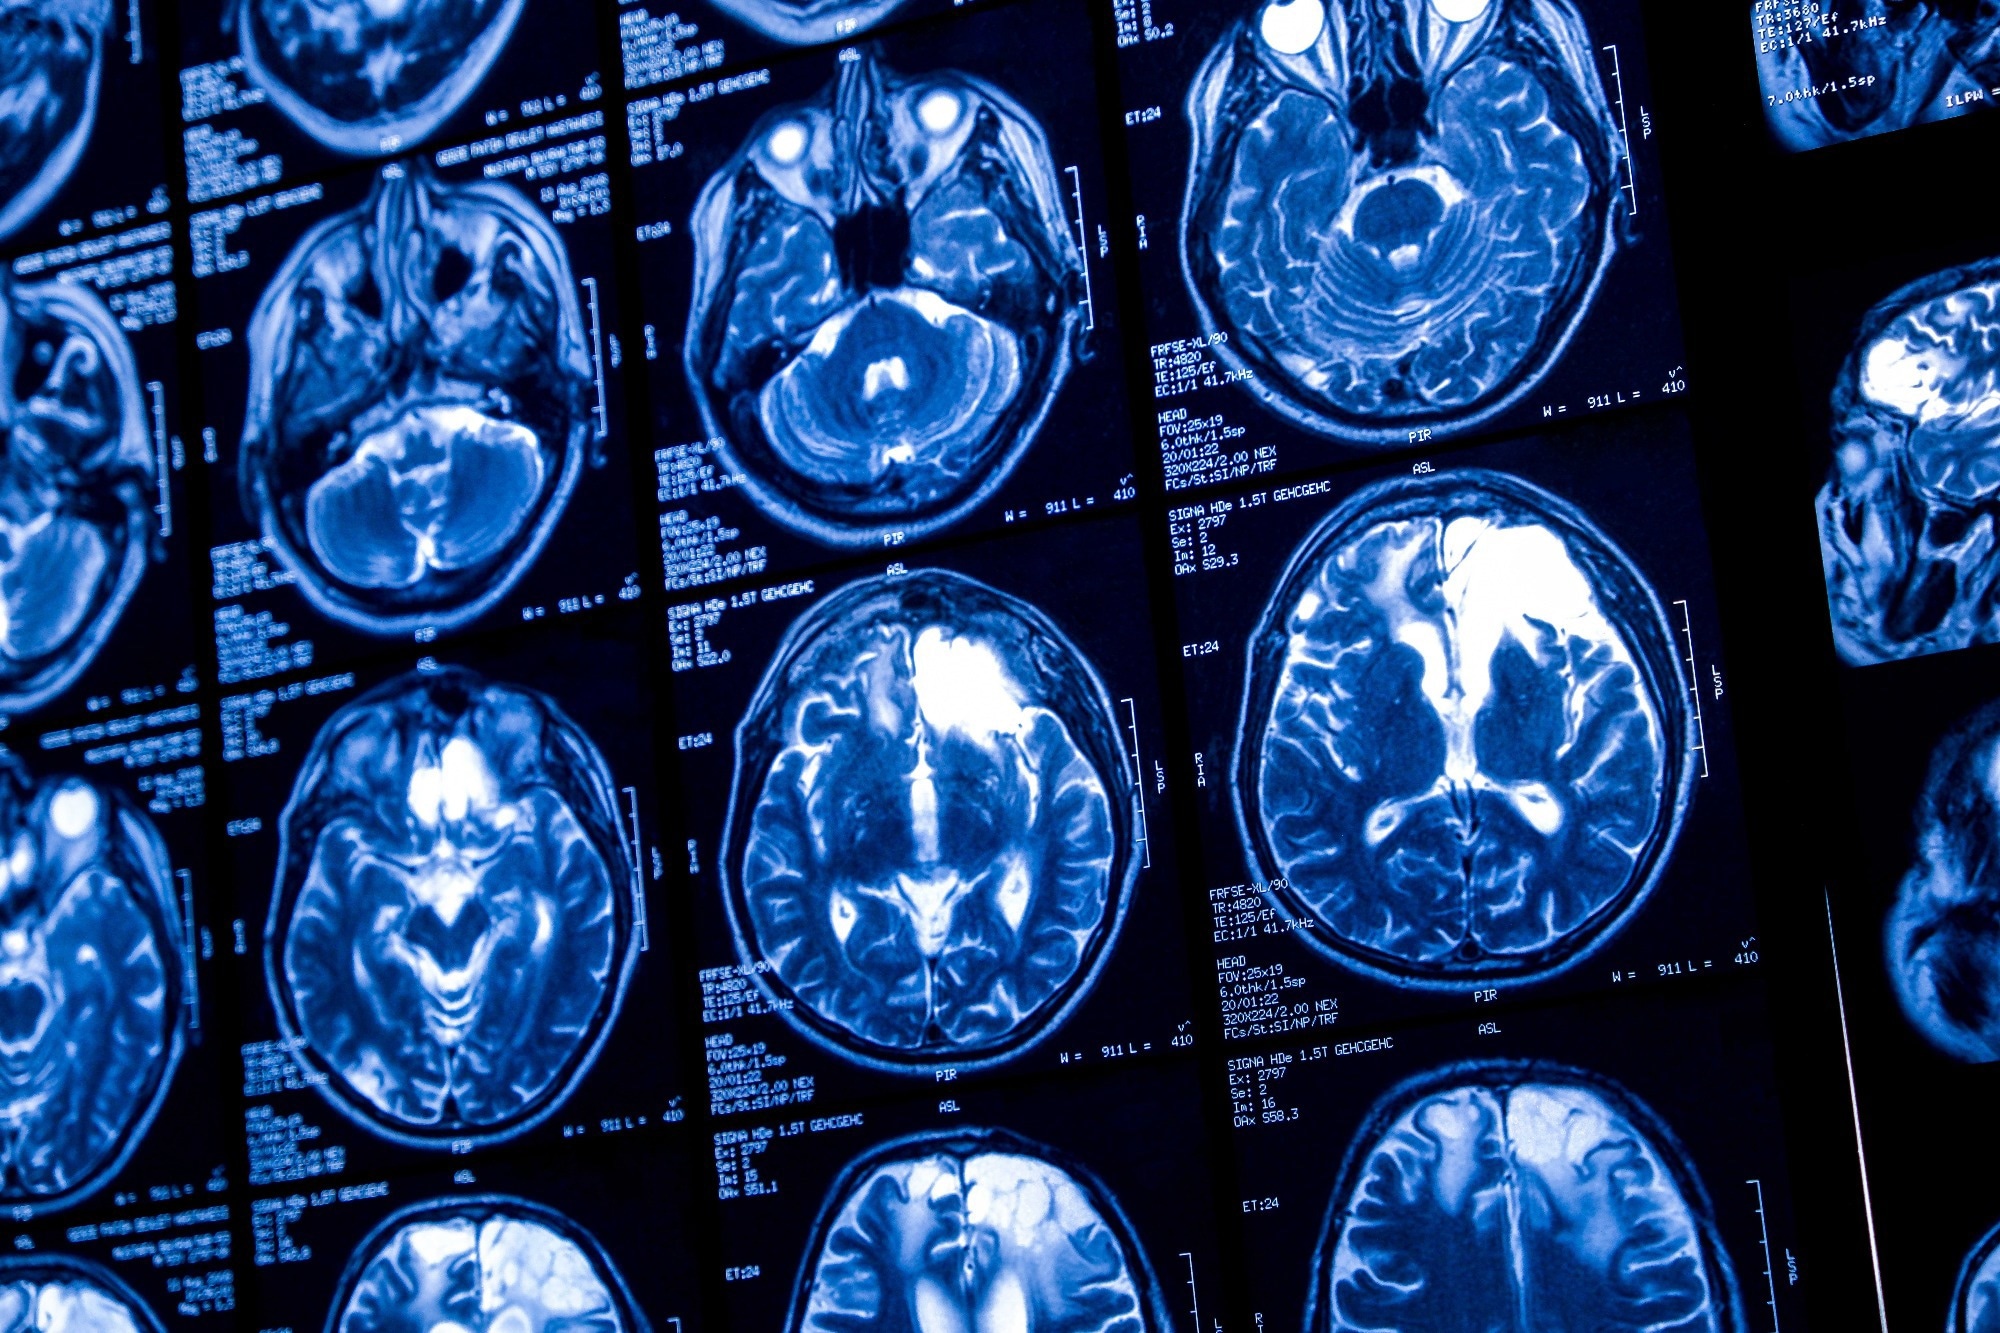

Study: Deep learning and transfer learning for brain tumor detection and classification. Image Credit: Elif Bayraktar/Shutterstock.comStudy: Deep learning and transfer learning for brain tumor detection and classification. Image Credit: Elif Bayraktar/Shutterstock.com

In a recent study published in Biology Methods and Protocols, researchers examined the use of convolutional neural networks (CNNs) and transfer learning to improve brain tumor detection in magnetic resonance imaging (MRI) scans.

Using CNNs pre-trained on detecting animal camouflage for transfer learning, the study investigated whether this unconventional step could enhance the accuracy of CNNs in identifying gliomas and improve diagnostic support in medical imaging.